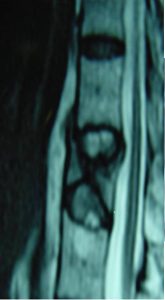

Εικόνα 3 (α,β,γ,δ,ε,): Η Μαγνητική τομογραφία αποκαλύπτει την ύπαρξη κατάγματος του 6ου Θωρακικού σπονδύλου. Με την καθοδήση του συστήματος πλοήγησης O-Arm πραγματοποιήθηκε η προώθηση των ειδικών trocar διαυχενικά εντός των σπονδυλικών σωμάτων μέσω των οποίων έγινε η έγχυση Polymethylmethacrylate (P.M.M.A.) στο σπονδυλικό σώμα αμφοτερόπλευρα ενώ είχε ήδη ληφθεί οστικό υλικό για βιοψία.

Εικόνα 3 (α,β,γ) : Προεγχειρητική Μαγνητική Τομογραφία, πλαγία λήψη ακολουθία Τ2, καταστροφή του οσφυϊκού σπονδύλου συνεπεία μετάστασης από το μυελό. Δια κυφοπλαστικής (β,γ) πραγματοποιήθηκε αποκατάσταση του σπονδυλικού σώματος.